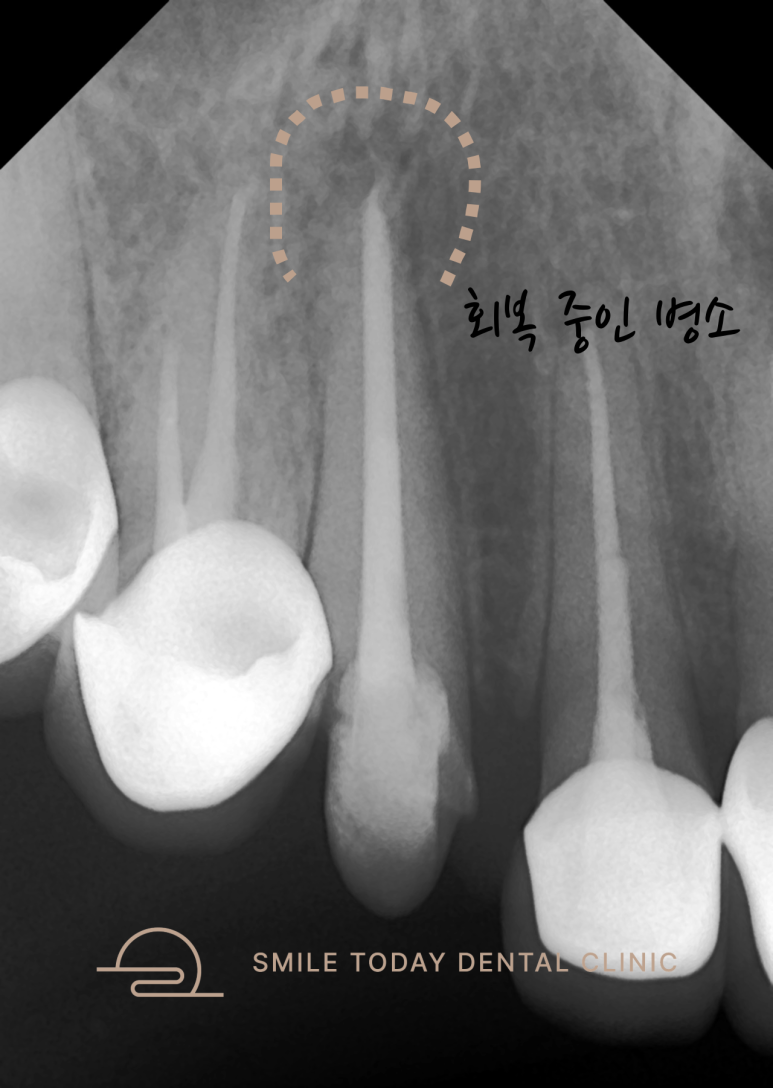

포스트를 완전히 제거한 후,

뿌리 끝까지 파일이 도달하는 것을

엑스레이로 확인했습니다.

또한, 이전 치료에서 길이를 짧게 설정했던 부분도

이번에는 정확히 맞춰 진행하여

더 나은 예후를 기대할 수 있는 상태가 되었습니다.

🦷 치료 결과

- 염증 부위가 불규칙하게 밝아진 것은

뼈가 회복되기 시작한 신호입니다. - 완벽한 밀봉으로 인해 자연치유가 시작됩니다.